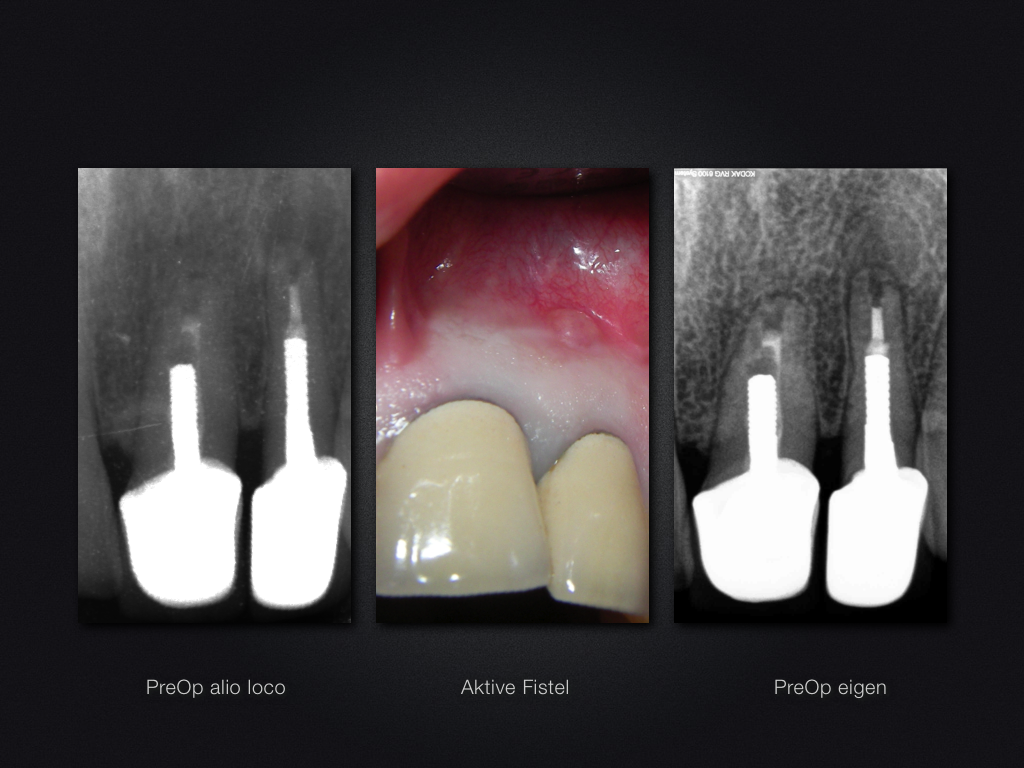

21 22 D.001

Revisions-Recall nach 3 Jahren